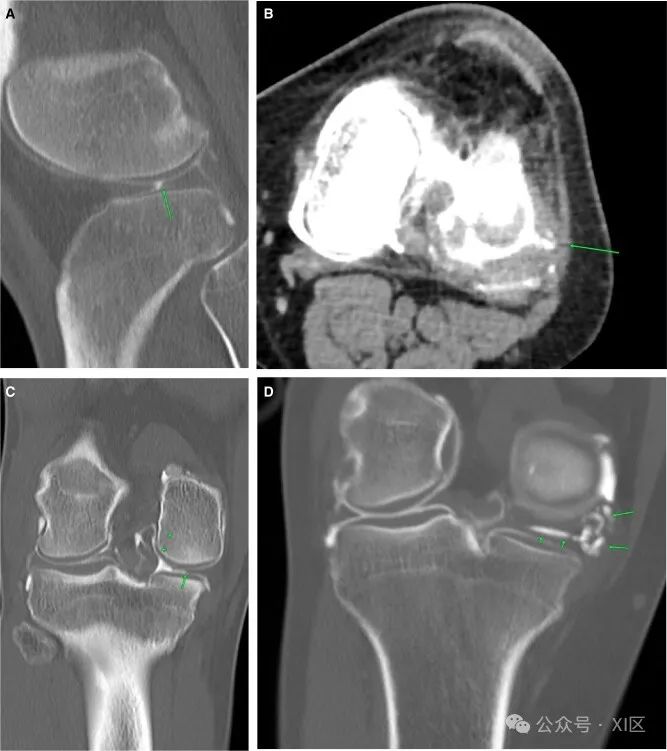

这些是一组与关节中晶体沉积有关的关节疾病,其中痛风最常见,焦磷酸钙二水合物晶体沉积病(CPPD)不太常见。膝关节是痛风的常见部位。规划前的图像显示软组织钙化和侵蚀,从微小病灶到广泛侵蚀不等(图9A和B)。慢性痛风在关节周围区域产生密集钙化。所有怀疑痛风的患者都应接受关节抽吸以进行晶体鉴定。手术台上评估通常显示血清液,应进行抽吸。关节造影图像可以将单个钙化移位,从而更好地解释微小病例。在严重的病例中,关节完全闭塞,没有任何造影剂填充关节间隙。如果关节内没有足够的液体,抽吸贝克氏囊肿进行晶体分析是非常有用的。CPPD在计划前CT上更为明显,半月板和关节软骨钙化(图9C)。同样,在手术台上评估中发现的任何液体都可以送去进行晶体分析。这一发现的鉴别诊断是退行性半月板钙化,这种钙化只发生在半月板中,而不发生在关节软骨中。

图9 晶体性关节病:(A)膝关节内侧(箭头)和外侧(箭头)广泛的软组织钙化,提示痛风。(B) 轴位图像显示广泛钙化(箭头)。(C) 和(D)关节造影后和关节造影前图像显示半月板钙化(箭头),提示CPPD。骨肿瘤